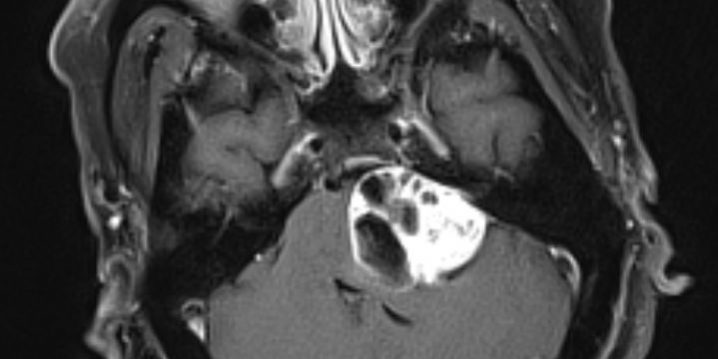

Η μετεγχειρητική μαγνητική τομογραφία εγκεφάλου (βλ. εικόνα) επιβεβαιώνει την πολύ καλή εξαίρεση του όγκου και την πλήρη αποσυμπίεση του εγκεφαλικού στελέχους.

Η μετεγχειρητική μαγνητική τομογραφία επιβεβαιώνει την αφαίρεση του όγκου και την αποσυμπίεση του στελέχους.